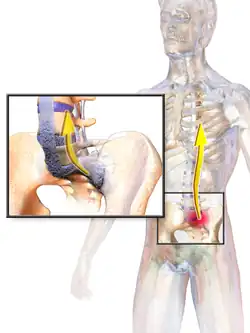

Ankylosing spondylitis (AS) is a type of arthritis from the disease spectrum of axial spondyloarthritis.[5] It is characterized by long-term inflammation of the joints of the spine, typically where the spine joins the pelvis.[2] With AS, eye and bowel problems—as well as back pain—may occur.[2] Joint mobility in the affected areas sometimes worsens over time.[2][6] Ankylosing spondylitis is believed to involve a combination of genetic and environmental factors.[2] More than 90% of people affected in the UK have a specific human leukocyte antigen known as the HLA-B27 antigen.[7] The underlying mechanism is believed to be autoimmune or autoinflammatory.[8] Diagnosis is based on symptoms with support from medical imaging and blood tests.[2] AS is a type of seronegative spondyloarthropathy, meaning that tests show no presence of rheumatoid factor (RF) antibodies.[2]

AS can occur in any part of the spine or the entire spine, often with pain localized to either buttock or the back of the thigh from the sacroiliac joint. Arthritis in the hips and shoulders may also occur. When the condition presents before the age of 18, AS is more likely to cause pain and swelling of large lower limb joints, such as the knees.[13] In prepubescent cases, pain and swelling may also manifest in the ankles and feet where heel pain and enthesopathy commonly develop.[13] Less common occurrences include ectasia of the sacral nerve root sheaths.[14]

"Bamboo spine" develops when the outer fibers of the fibrous ring (anulus fibrosus disci intervertebralis) of the intervertebral discs ossify, which results in the formation of marginal syndesmophytes between adjoining vertebrae.

The earliest changes demonstrable by plain X-ray shows erosions and sclerosis in sacroiliac joints. Progression of the erosions leads to widening of the joint space and bony sclerosis. X-ray spine can reveal squaring of vertebrae with bony spur formation called syndesmophyte. This causes the bamboo spine appearance. A drawback of X-ray diagnosis is the signs and symptoms of AS have usually been established as long as 7–10 years prior to X-ray-evident changes occurring on a plain film X-ray, which means a delay of as long as 10 years before adequate therapies can be introduced.[25]